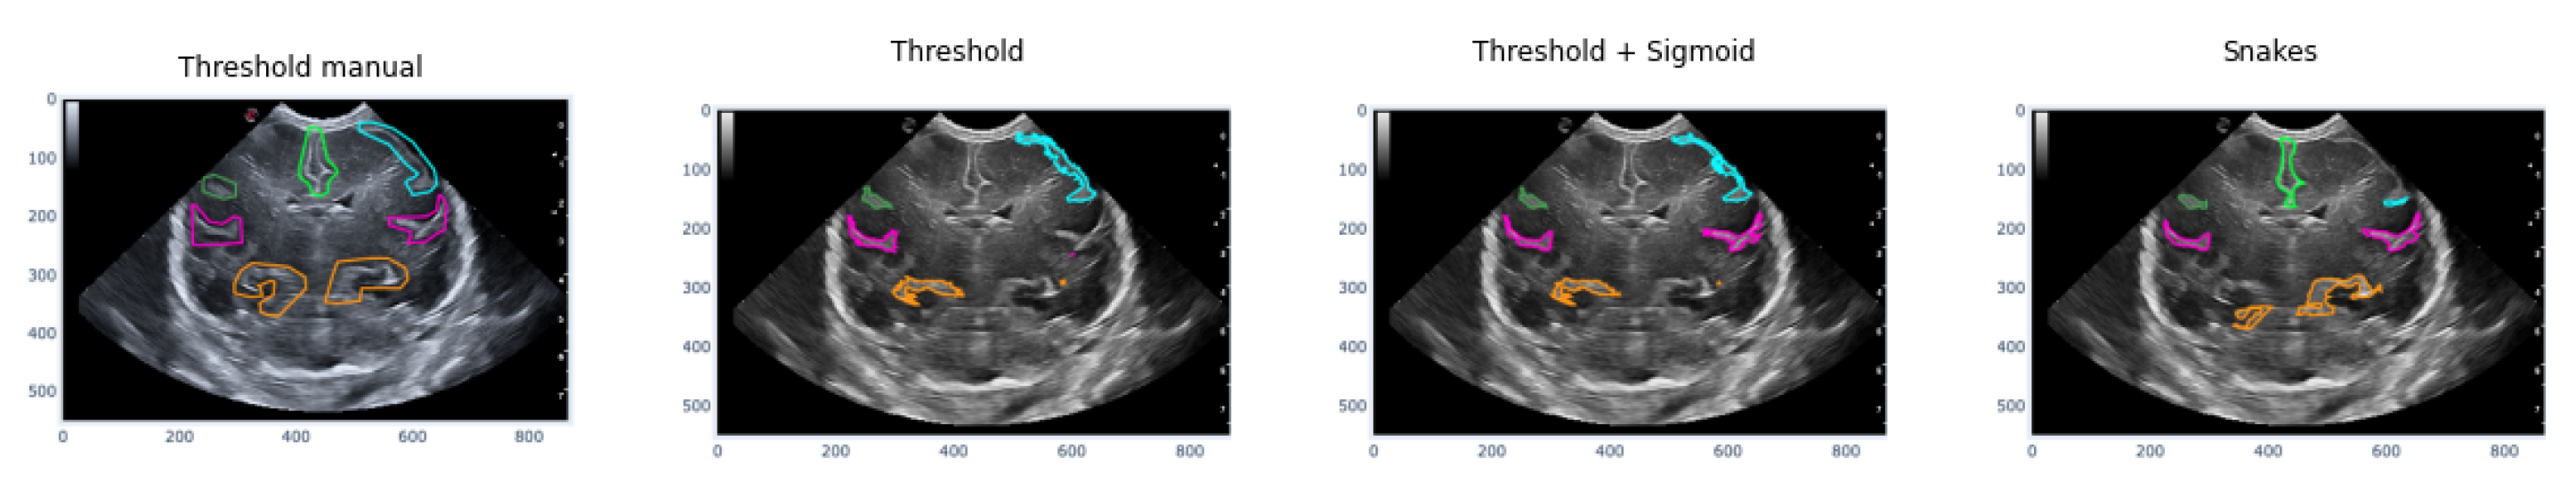

The first case analyzed used an image of a premature infant at week 29 of gestation, in which several furrows have been segmented, as shown in Figure 16. Each color represents a particular groove in which manual segmentation has been applied in the first image or one of the methods applied in the following images, in the order of Threshold, Sigmoid + Threshold, and Snakes.

Figure 16 shows that when applying the Threshold method (second and third images), there is not much variation in obtaining the segmentation. However, applying the sigmoid preprocessing was able to segment the pink-colored groove on the right side. In contrast, the Snakes method (fourth image) was able to segment an orange-colored groove in the lower right part that had not been segmented with the Threshold method.

Figure 16. Examples of segmentation of different grooves in an ultrasound scan of a baby at week 29 of gestation and c4 coronal section